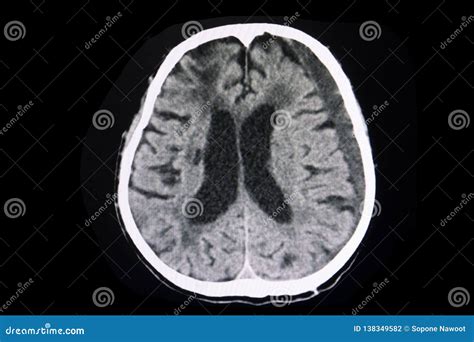

• Chronic Subdural Hemorrhage: Occurs more than 20 days after the injury and appears hypodense on CT images.

• Distinguishing between acute, subacute, and chronic subdural hemorrhages based on CT images.

• Identifying small or subtle hemorrhages that may not be immediately apparent on CT scans.

These challenges highlight the importance of experienced radiologists and neurologists in interpreting Subdural Hemorrhage CT Images.

Case Study 2: A 70-year-old patient with a history of falls presented with confusion and weakness on one side of the body. A CT scan showed a hypodense collection consistent with a chronic subdural hemorrhage. The patient was managed conservatively with close monitoring and supportive care, and follow-up CT scans showed gradual resolution of the hemorrhage.